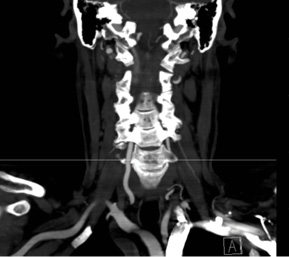

This patient is a 58 year-old female radiology technician with chronic, intractable neck pain, right > left arm radicular pain, and progressive weakness. At one point her symptoms worsened so acutely, she presented to the emergency department for acute triage with cervical CT angiogram, which showed advanced spondylosis at the C6/7 level.

The combination of the chronic problem with acute worsening of symptoms required decompression and stabilization at C6/7. Typically, at this patient age, with this advanced level of spondylosis at the C6/7 level, I would proceed with an instrumented fusion. However, this patient was very active and wanted to optimize her quality of life as possible with this surgery.

Patient is a healthy, active 58 year-old female, though with advanced degenerative spondylosis at a low cervical level. The patient had favorable anatomy with a long neck and low shoulders to facilitate intraoperative visualization. Fusion was appropriate in this case, but intraoperatively, though we were prepared for this possiblity, the disk space was well-preserved and mobilized without major modification of the endplates. The postoperative flexion and extension radiographs showed movement at the spinous processes of C6/7 and good function of the prodisc C Vivo prosthesis. The adjacent C5/6 level also shows degenerative spondylosis. By optimizing the mobility of the C6/7 level I anticipate the patient will have an improved trajectory for her cervical spine function throughout her life.